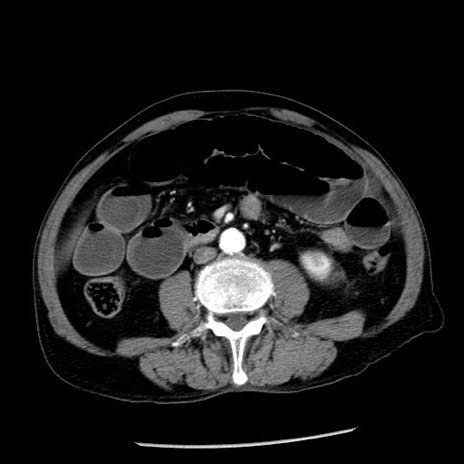

冠状断像

【症例】80歳代男性

【主訴】嘔吐

【現病歴】昨晩2回嘔吐あり、今朝になっても嘔吐あり。来院。

【既往歴】胃潰瘍

【身体所見】意識清明、BT 37.6℃、BP 166/95mmHg、HR 100bpm、SpO2 97%、腹部:平坦・軟、腸蠕動音聴取良好、圧痛なし。

【データ】WBC 21900、CRP 1.46